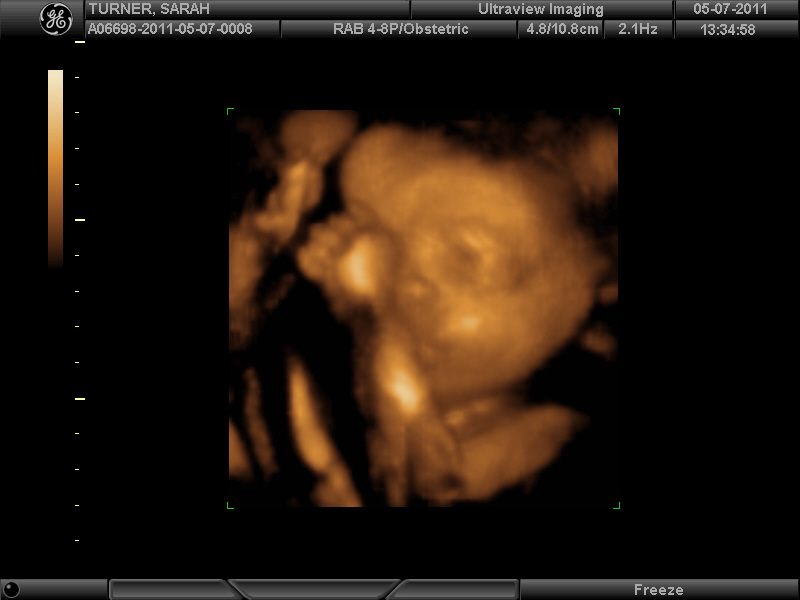

This morning I got a great Mother's Day gift. I got to see my son's face for the first time.

It was squished and a little distorted, and the little guy was absolutely determined to hide behind his arm, but after a little coaxing from the sonographer we got a few good looks. We were able to determine without a doubt that he is, in fact, a he. (I do have photographic proof, but for the sake of his dignity you'll just have to trust me.) This puts my mind at ease considering I have this recurring dream where Sam actually ends up being "Samantha" and there is mass chaos while I try to exchange baby clothes and redecorate the nursery. It looks like he weighs about three pounds right now which is right on track. He had both legs flipped up so his feet were by his head. I don't know how that can be comfortable, but he seemed quite content.

The big question of the day was "whose nose will he have?". I think it's safe to say that the Jordan nose has been passed down from Papa to Mommy to Sam. Take a look and see what you think...

We got a recording of a good strong heartbeat (about 150 bpm). I don't think I'll ever get tired of hearing that sound. (Unfortunately, I couldn't post the video, but here's a snapshot.)